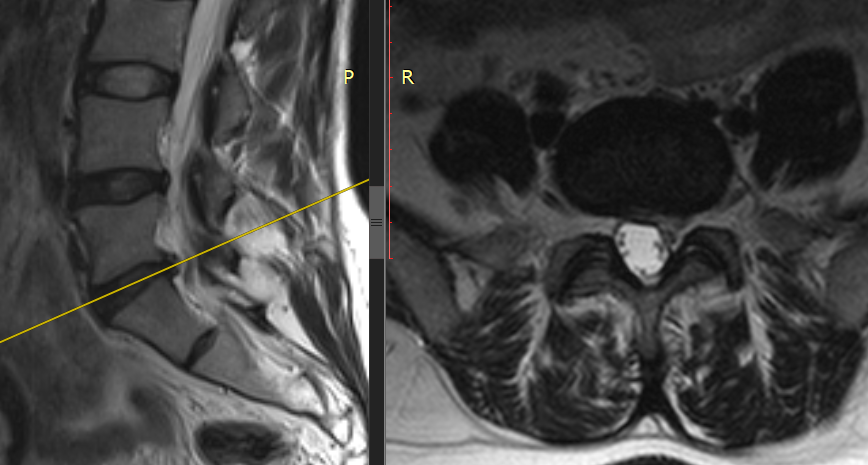

Обследования выявили грыжу межпозвонкового диска на уровне L5-S1. Консервативная терапия не дала должного эффекта, и Венера Сагдиева обратилась на консультацию к врачу-нейрохирургу Новосибирского НИИТО им. Я.Л. Цивьяна Минздрава России.

«Грыжа — это выпячивание ядра межпозвонкового диска в позвоночный канал в связи с нарушением целостности фиброзного кольца. Она возникла у пациентки вследствие дегенеративных изменений в межпозвонковом диске.

Это вызывает компрессию нерва в позвоночном канале — и у человека появляются боли и онемение в ногах, нарушения в работе определённой группы мышц», — объясняет к.м.н., заведующий нейрохирургическим отделением №1 ННИИТО Шамиль Ахметьянов.

Грыжа стала причиной боли и онемения в ногах. Снимок ДО операции